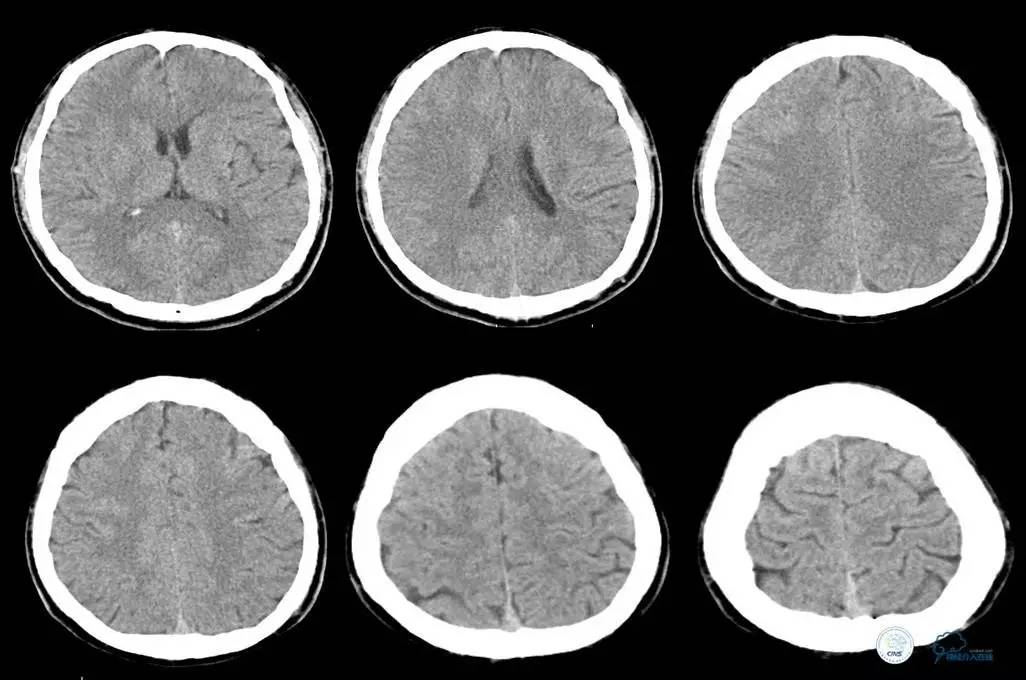

辅助检查:头CT未见异常。

初步诊断:

脑梗死——右颈内动脉系统

胸闷、胸痛待查,主动脉夹层?

治疗原则:急查主动脉CT。

中间诊断:

主动脉夹层 De Bakey Ⅰ型

脑梗死